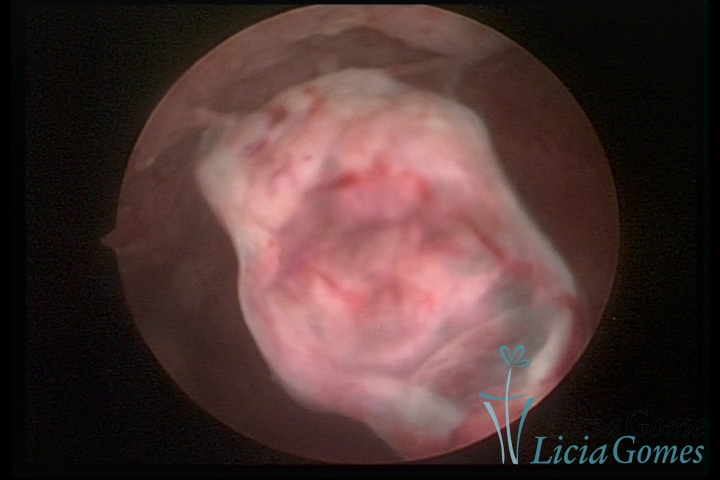

Septate uterus